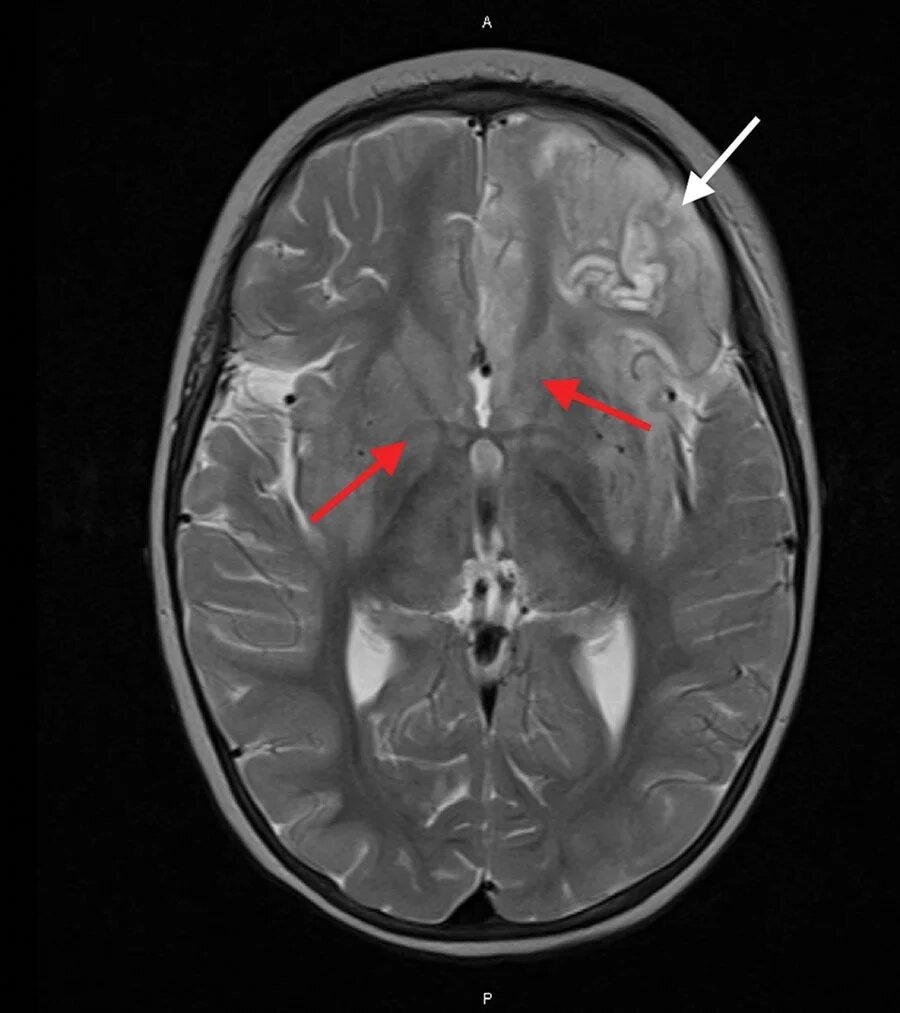

یک بررسی جدید شواهدی از وجود پک ویروس انسانی در مغز افراد مبتلا به بیماری پارکینسون پیدا کرده است، اما در مغز افراد بدون این بیماری عصبی چنین شواهدی وجود ندارد.